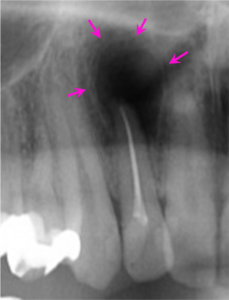

治療前

右上の前歯の歯茎から膿が出ることを主訴にご来院されました。

右上2番の歯の根の先に炎症があり膿が出ていたので、しっかりとした根の治療(精密根管治療)を提案し、患者様の合意を頂き治療を行うこととなりました。

左図のレントゲン写真では右上2番の根の先に炎症があり大きく骨が溶けている部分があります(矢印部) 。